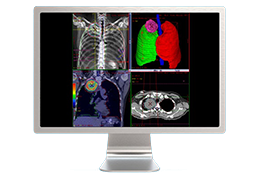

Visualization Tools

Parametric and non-parametric statistical maps may be superimposed both on the original functional scans as well as onto T1-weighted 2D or 3D anatomical reference scans. Time courses of selected regions-of-interest (ROIs) are available both in 2D and 3D representations. Statistical maps may be computed either in the 2D or 3D representation since structural as well as functional 4D data (space x time) are transformed into Talairach space. This allows you to compare activated brain regions across different experiments and across different subjects

Segmentation

Segmentation of tissue (e.g., isolating the brain, differentiating gray and white matter) is performed using region-growing methods, filter operations as well as the application of 3D templates. Using the mouse it is very easy to explore a 3D volume with superimposed pseudocolor-coded statistical maps in a four-window representation showing a sagittal, coronal, transversal and oblique section. Based on a (segmented) 3D data set a three-dimensional reconstruction of the subjects' head and brain can be calculated and displayed from any specified viewpoint using volume or surface rendering.

Volume Rendering

Volume rendering is performed with a very fast ray casting algorithm; lightning calculations are based on Phong-shading. Surface rendering of reconstructed surfaces is performed using OpenGL. Using texture mapping, a reconstructed surface (e.g., head or brain) may be sliced in real time, showing both surface and volume data at the same time. Initial polygon meshes serve as the basis for surface finding, cortex inflation and cortex flattening computations.